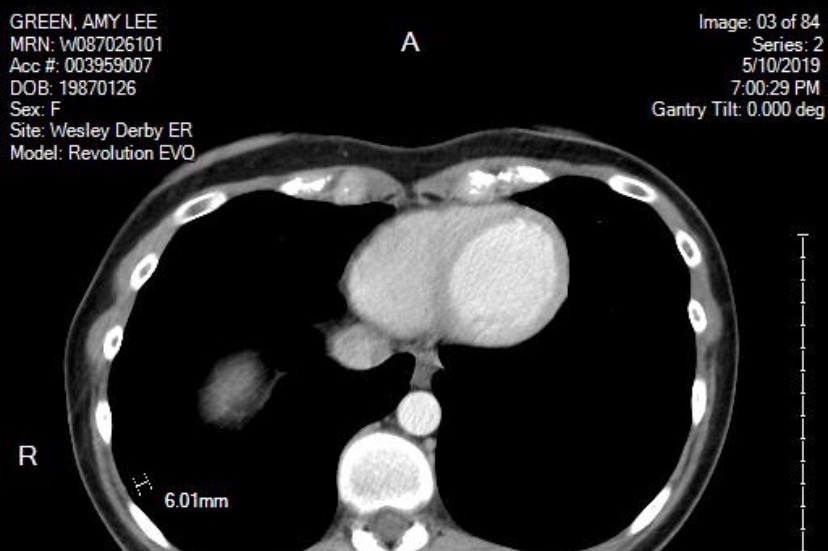

Unfortunately, the hysterectomy did not stop the pain or the spread of the disease. In May tests showed a small nodule (pictured below) had formed on her right lung and a one centimeter cyst was found on her right kidney. By the beginning of August another cyst was discovered on the same kidney.

Unfortunately, the hysterectomy did not stop the pain or the spread of the disease. In May tests showed a small nodule (pictured below) had formed on her right lung and a one centimeter cyst was found on her right kidney. By the beginning of August another cyst was discovered on the same kidney.